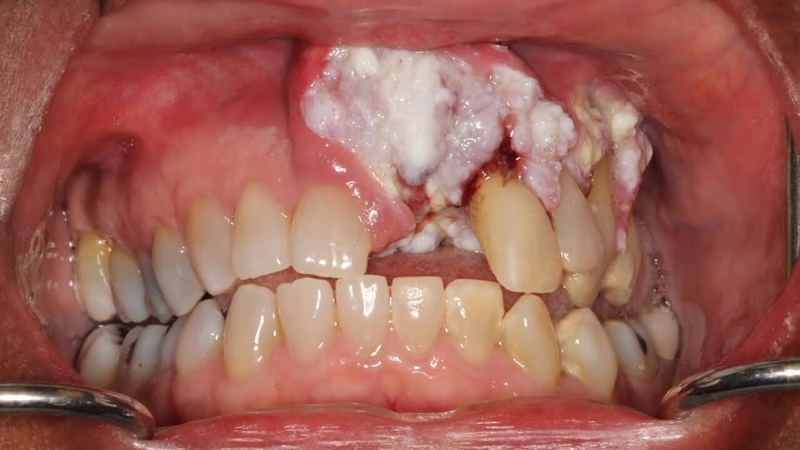

/https://cms-prod.s3-sgn09.fptcloud.com/ung_thu_nuou_rang_co_chua_duoc_khong_1_e3f7538eb2.jpg) Hình ảnh ung thư nướu răng

Hình ảnh ung thư nướu răng Ung thư nướu răng thuộc nhóm bệnh ung thư trong miệng. Bệnh phát sinh ra do sự phát triển quá mức và không theo quy luật của một số tế bào biểu mô vảy do nhiều yếu tố nguy cơ khác nhau gây nên.

Nốt nhiệt miệng lâu lành là dấu hiệu của ung thư nướu răngTrên nướu có thể xuất hiện các khối u nhỏ, có màu sắc đỏ sậm, bề mặt sần sùi, kích thước có thể to hoặc nhỏ khác nhau. Những khối u nướu có thể gây đau, khi chạm nhẹ cũng dễ chảy máu. Khối u nướu thường tăng kích thước và số lượng theo thời gian. Đây chính là một dấu hiệu ít gặp nhưng đặc trưng cho bệnh, khi có dấu hiệu này cần đi khám để phát hiện sớm ung thư nướu.